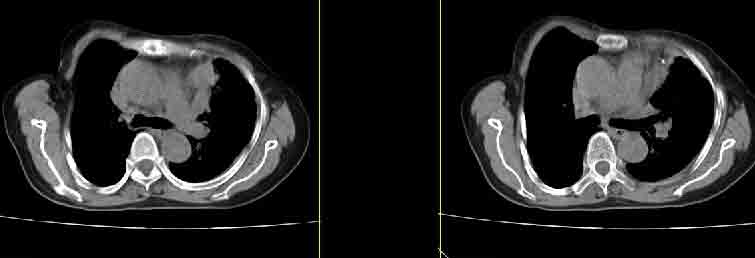

女77岁因左侧胸痛伴咳嗽入院;提示:病灶平扫45hu,强化145hu补充:双肺内未闻及干湿罗音

我的诊断意见:左肺上叶前段肺癌伴节段性不张。

在不张的肺内见到不规则的软组织,而且强化是不均匀的(该点可能是我的图像作得不好的原因)。

左上肺前段可见分叶团块影,强化明显,周围见带状不张影,右肺结节,左肺沿肺纹模糊片状影,考虑左上肺占位,肺癌可能性大。

考虑左肺上叶前段肺癌伴节段性不张、肺内转移,建议薄层扫描。